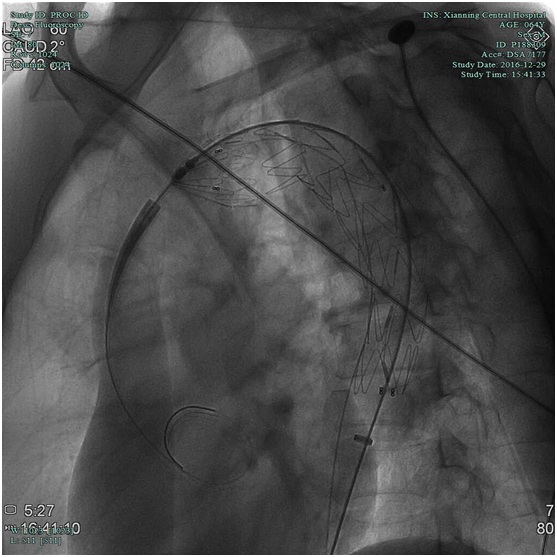

血管外科:胸腹主动脉夹层支架植入术

近日,血管外科在外请专家指导下成功行胸腹主动脉夹层覆膜支架植入术2例,其中一例患者已顺利出院,结束了我院治疗胸腹主动脉夹层需要转院的历史,血管外科将进一步发展血管外科腔内治疗技术和结合手术治疗的血管杂交技术。